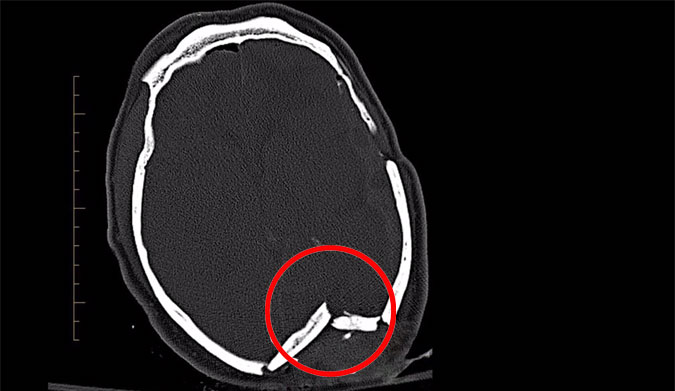

Pascal Dattler, a local Byron Bay surfer, was the victim of an unfortunate run-in with a leashless balsa wood fish while surfing The Pass. “It just punched straight through my head,” said Pascal. “They had to stitch up the membrane of my brain and smooth out bits of my brain. They had to reconstruct the hole of my skull with metal plates and bolts.” Fortunately, Pascal made a full recovery, but his injury is just one example among thousands we should consider while discussing the dangers of not wearing a leash.